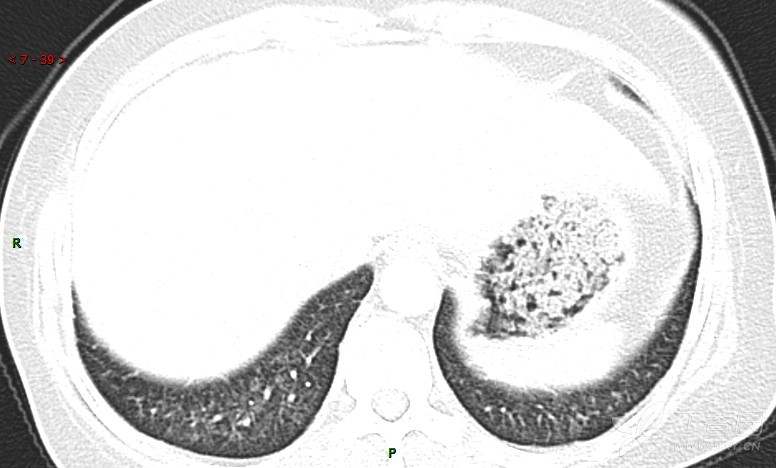

女性,58岁,阵发性咳嗽2月,加重1月。

糖类抗原15-3 70.7 U/ml ↑ 0--31.3

癌胚抗原 57.12 ng/mL ↑ 0--5

糖抗原125 166.8 U/ml ↑ 0--35

细胞角蛋白19片段测定 8.32 ng/ml ↑ ≤3.3

糖抗原199 901.79 U/ml ↑ 0--37

AFP、NSE(-)

患者活检肺组织后行PET/CT检查